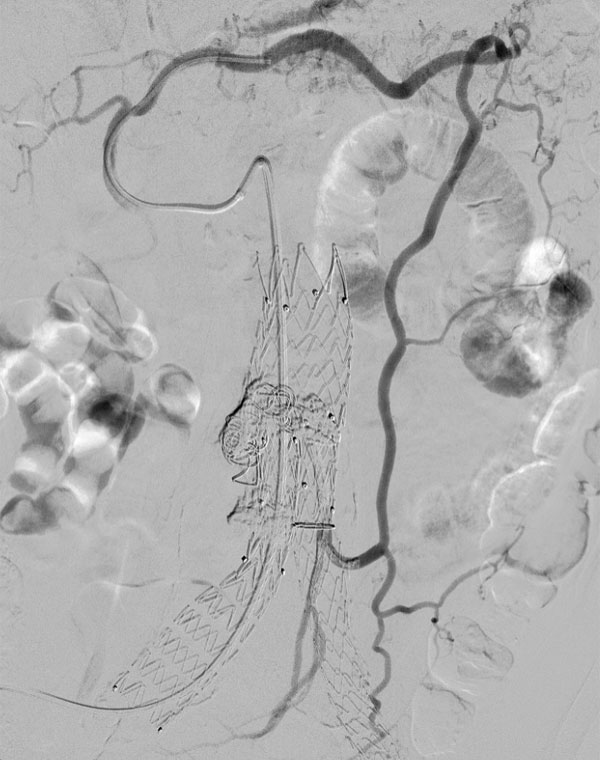

Μετά από την ενδαγγειακή επέμβαση για ανεύρυσμα κοιλιακής αορτής στη πλειοψηφία των ασθενών ο σάκος του ανευρύσματος θρομβώνεται πλήρως. Σε ορισμένες περιπτώσεις αυτό δεν συμβαίνει διότι αγγεία τα οποία φυσιολογικά υπάρχουν στο πίσω μέρος (οσφυϊκές αρτηρίες) ή στο μπροστινό μέρος του ανευρύσματος (κάτω μεσεντέριος αρτηρία) μπορεί να συνεχίσουν να τροφοδοτούν με αίμα τον ανευρυσματικό σάκο. Αυτό ονομάζεται ενδοδιαφυγή τύπου ΙΙ. Στην συντριπτική πλειοψηφία των ασθενών με ενδοδιαφυγή τύπου ΙΙ δεν απαιτείται καμία παρέμβαση παρά μόνο τακτική παρακολούθηση με αξονική αγγειογραφία ή υπέρηχο. Εάν διαπιστωθεί αύξηση του ανευρύσματος τότε πρέπει να διενεργηθεί εμβολισμός όλων των αγγείων που συμμετέχουν στην ενδοδιαφυγή καθώς και του ανευρυσματικού σάκου.

Εμβολισμός ενδοδιαφυγής από κάτω μεσεντέριο αρτηρία